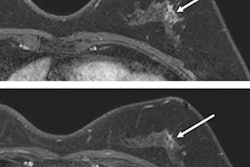

The test set included 1,467 cancer-free exams and 15 with cancer. The AI algorithm detected all 15 cases with cancer and triaged 20% of the cancer-free exams to an abbreviated interpretation worklist for a radiologist. The remaining 80% of exams were triaged for full interpretation by a radiologist.

In a reader study comparing the performance of radiologists with the AI algorithm, 42 of the 50 MRI exams were cancer-free and eight included cancer. All eight cancer exams were identified by both the radiologists and the AI algorithm.

Of the 42 cancer-free exams, nine were triaged to an abbreviated worklist for radiologists and 33 were triaged to full radiologist interpretation. The radiologists dismissed 39 (92%) of the 42 cancer-free exams and flagged three (7%) for biopsy.